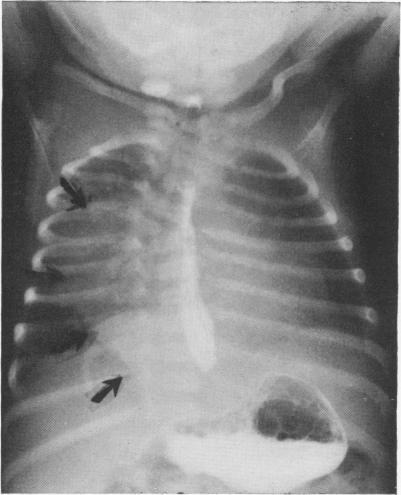

https://cdn.ncbi.nlm.nih.gov/pmc/blobs/5a03/1397071/d39e137615ad/annsurg00402-0089-a.jpg